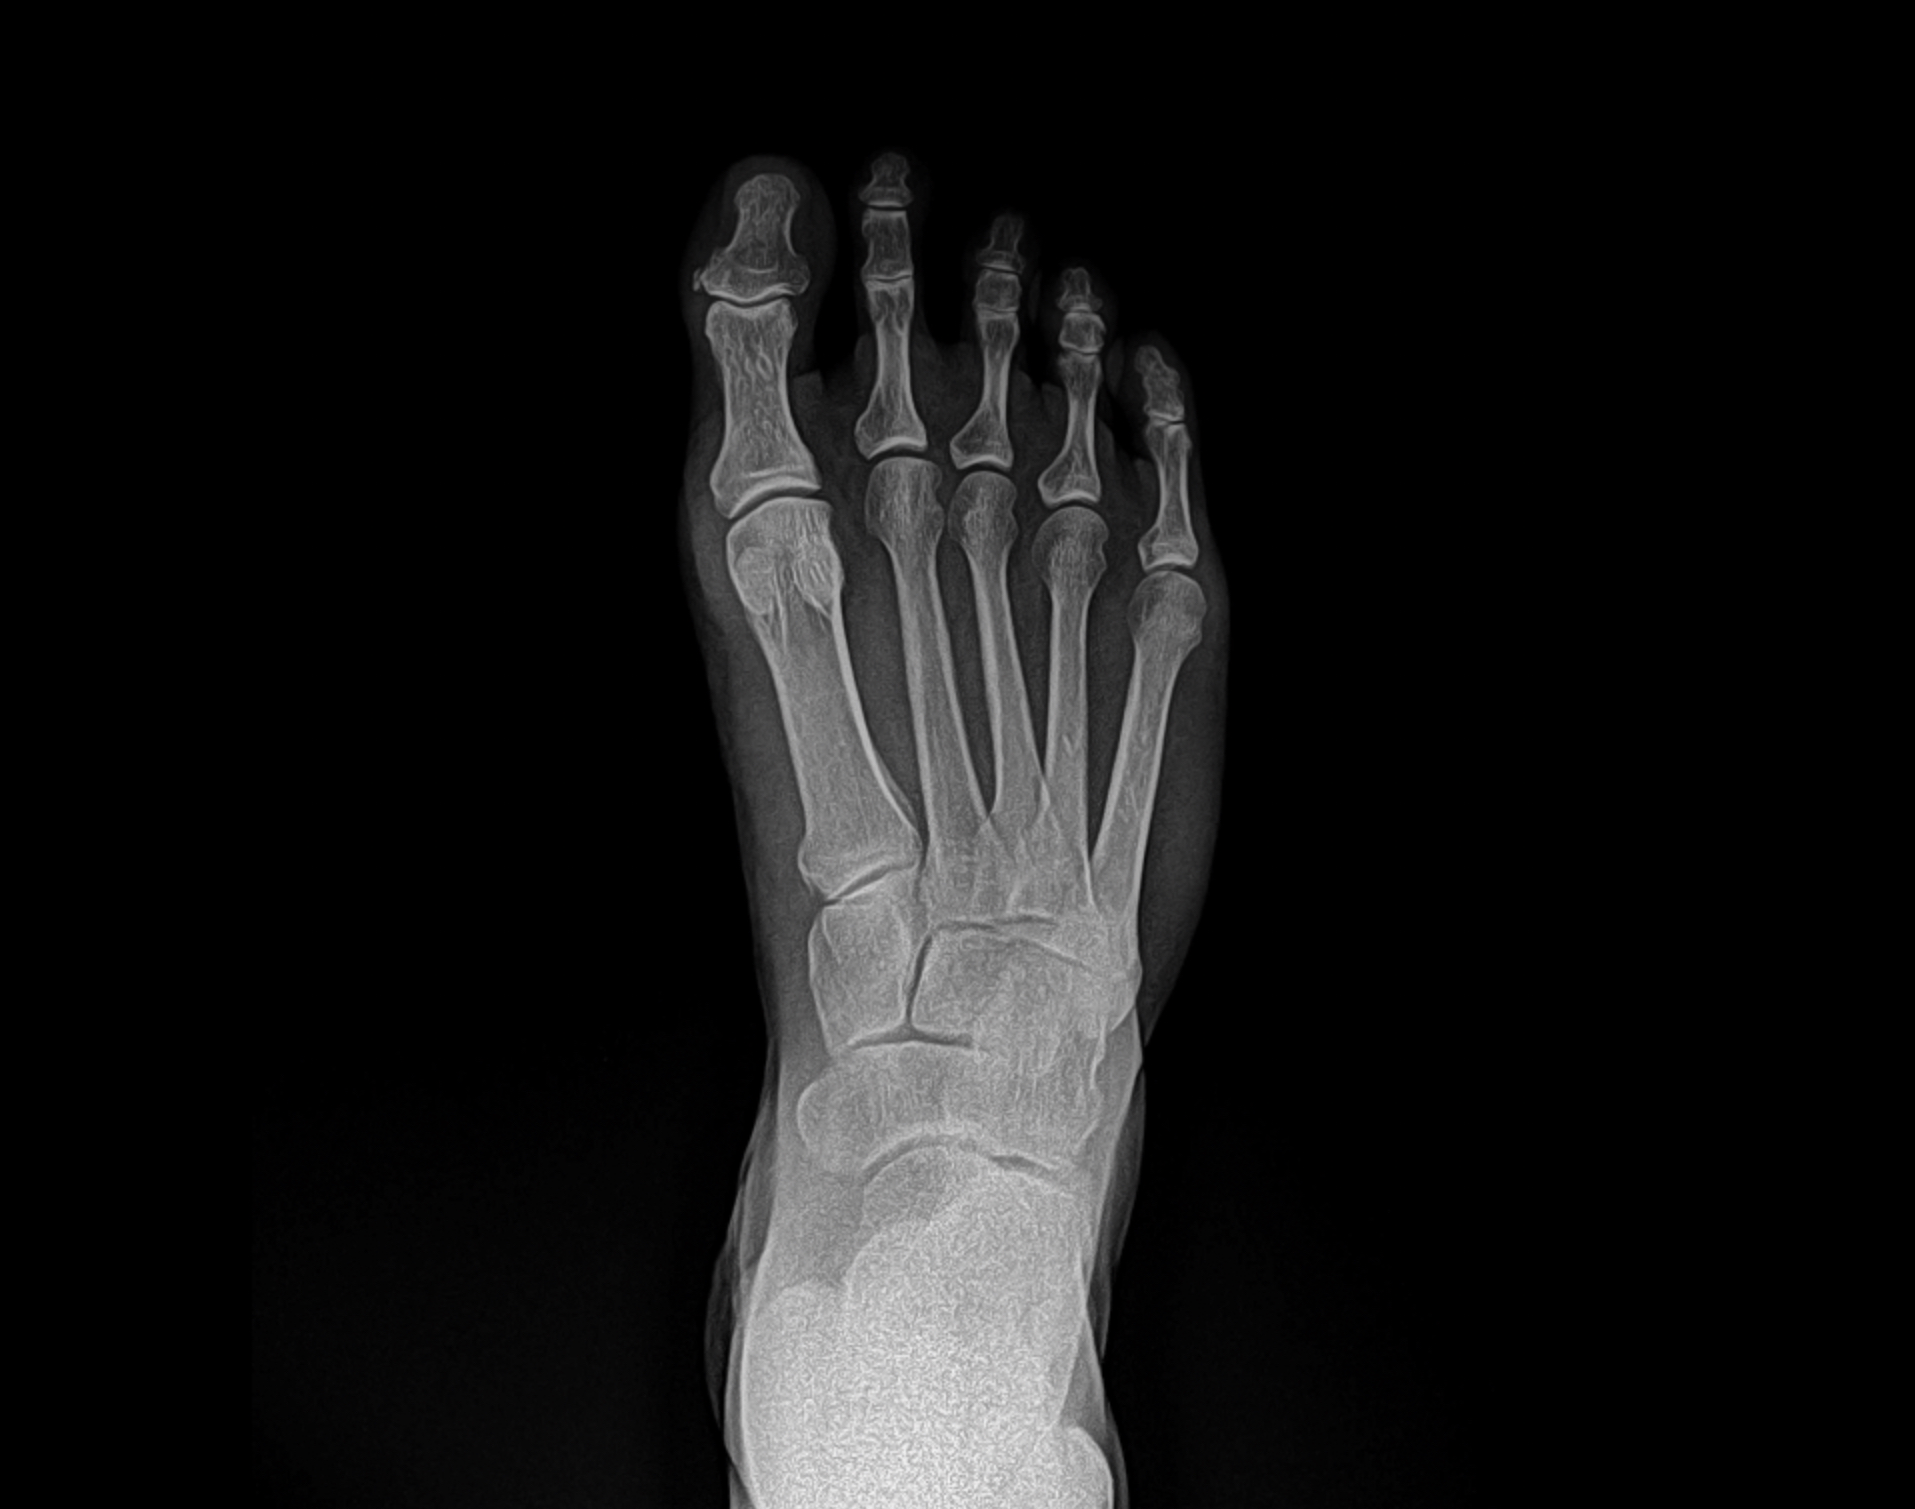

Flatfoot deformity

Patient 1

Patient 2